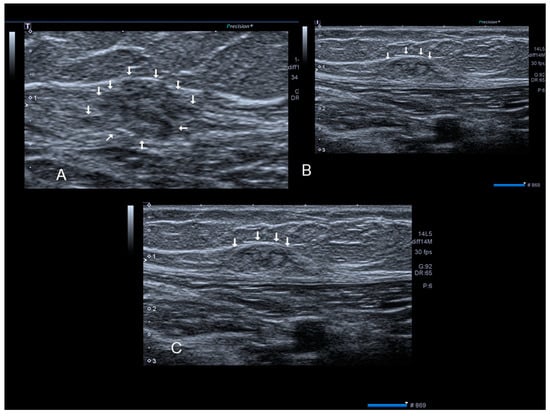

2.4. Rectus Abdominis Endometriosis

Endometriosis of the rectus muscle is an extremely rare localization of extra-pelvic endometriosis [19]. Ultrasonography usually demonstrates a heterogeneous hypoechogenic formation with indistinct edges [20] (Figure 6, Figure 7 and Figure 8). To help in the diagnosis, if the patient moves her legs alternatively during the examination the operator can easily visualize the muscular layers.

Figure 7. A rectus abdominis endometriosis (white arrows) in a woman without previous surgery (A,B).